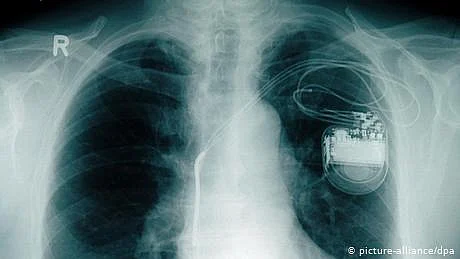

ماہرین کے مطابق یہ پیس میکر دراصل ایک طرح کا بہت چھوٹا سا جنریٹر ہے، جسے چینی اور امریکی ماہرین نے مل کر تیار کیا ہے۔ یہ پیس میکر کسی بھی عام پیس میکر کی طرح مریض کی سینے میں دل سے کچھ اوپر لگایا جاتا ہے اور وہ مریض یا مریضہ کے دل کی دھڑکن کو کنٹرول میں رکھتا ہے۔

اس انتہائی جدید پیس میکر کی خاص بات یہ ہے کہ یہ مریض یا مریضہ کی حرکت اور اس کے دل کی دھڑکن سے پیدا ہونے والی حرکی توانائی سے اپنی توانائی کی ضروریات پوری کرتا ہے اور اسی لیے اسے بیٹری کی کوئی ضرورت نہیں ہوتی۔